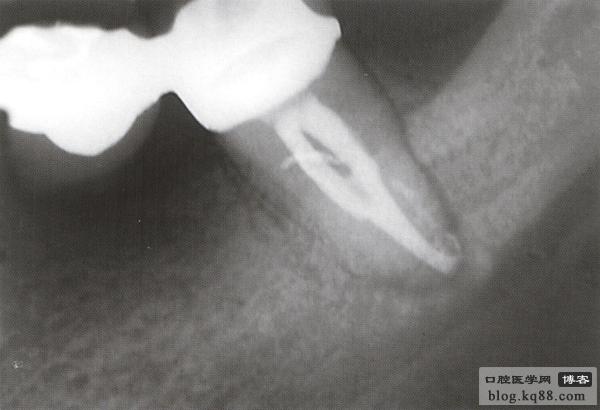

修復(fù)后出現(xiàn)根尖周炎 去除原根充物后試主尖

熱牙膠充填后 一年后復(fù)查病變愈合